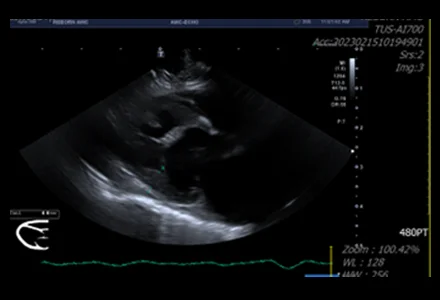

• 심장초음파

심장의 구조적 이상과 심실 기능, 판막 상태 등을 실시간으로 평가하는 핵심 검사입니다. 혈액의 흐름, 심장벽의 두께, 심장 크기 변화 등을 정밀하게 측정하여 대부분의 심장 질환을 진단합니다.

• 심장초음파 검사는 꼭 필요한가요? 아이에게 힘들지는 않나요?

심장초음파 검사는 심장의 구조와 기능을 직접 눈으로 확인하고 혈액의 흐름을 평가하여 대부분의 심장 질환을 정확하게 진단하는 데 가장 중요한 핵심 검사입니다.

대부분의 경우 마취 없이 진행 가능하며, 숙련된 의료진이 아이의 스트레스를 최소화하며 안전하게 검사하므로 크게 걱정하지 않으셔도 됩니다.